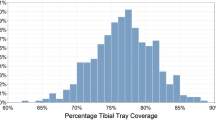

Kinematic alignment has gained interest in the last few years because of some recent randomized trials, and a national multicenter study showed that patients treated with kinematic alignment using patient-specific instrumentation reported significantly better pain relief, function, flexion and a more normal-feeling knee than patients treated with mechanical alignment [5,6,7,8,9]. In contrast to mechanical alignment, the target for kinematic alignment is to set the tibial component tangent to the varus-valgus plane and parallel to the posterior slope of the native proximal tibial joint [10, 11]. Although, kinematic alignment has a high rate of implant survival at two, three, and six-years [5, 6, 9, 12, 13], there are concerns that kinematic alignment predisposes the tibial component to high medial loads and varus failure because 75–80% are set in varus with respect to the mechanical axis of the tibia (Fig. 1) [14, 15].

This case control study was performed because there are concerns that kinematic alignment predisposes the tibial component to high medial loads and varus failure because 75–80% are set in varus with respect to the mechanical axis of the tibia (Fig. 1) [14, 15]. Accordingly, differences in radiographic measurements and clinical characteristics between patients with and without tibial component failure were determined to identify mechanisms of failure and propose strategies that might reduce the risk. The most important findings were that patients with a kinematically-aligned TKA: (1) have a low 0.3% incidence of early failure, (2) present with pain or instability from the mechanisms of posterior subsidence of the tibial baseplate or posterior edge wear of the insert, (3) are associated with 5° greater posterior slope of the tibial component, 6 kg/m2 greater pre-operative BMI and 15° less pre-operative flexion than a matched control cohort, and (4) that revision is successful in the short term by implanting a long-stemmed tibial component with less posterior slope or exchange to a thicker insert with retention of the cruciate-retaining femoral component.